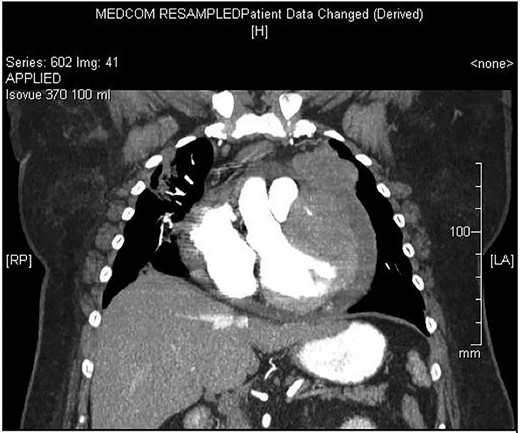

Chest X-ray found an enlarged cardiomediastinal silhouette with mild pulmonary edema (Fig. 1). A computed tomography angiography (CTA) of the chest to rule out pulmonary embolism (PE) was ordered. After the patient returned from imaging, she was found to have a heart rate of 178. Patient was awake, did not appear to be in any more distress and remained hemodynamically stable. Repeated ECG showed monomorphic ventricular tachycardia, with the patient remaining non-distressed. Patient was started on i.v. amiodarone, and urgent cardiology consult was obtained. A transthoracic echocardiogram depicted a large mass measuring 5 cm by 7 cm occupying the basal and mid portion of the anterior and lateral walls of the left ventricles with large pericardial effusion located at the lateral posterior wall of the heart, findings suggestive of impending tamponade (Fig. 2). CTA of the chest reported no acute PE with a large mass (10.5 × 7.5 × 9.5 cm3) occupying the anterior wall of the left ventricle and extending to the pulmonary outflow tract (Fig. 3).

Large ventricular mass measuring 10.5 × 7.5 × 9.5 cm3 invading epicardium and myocardium.